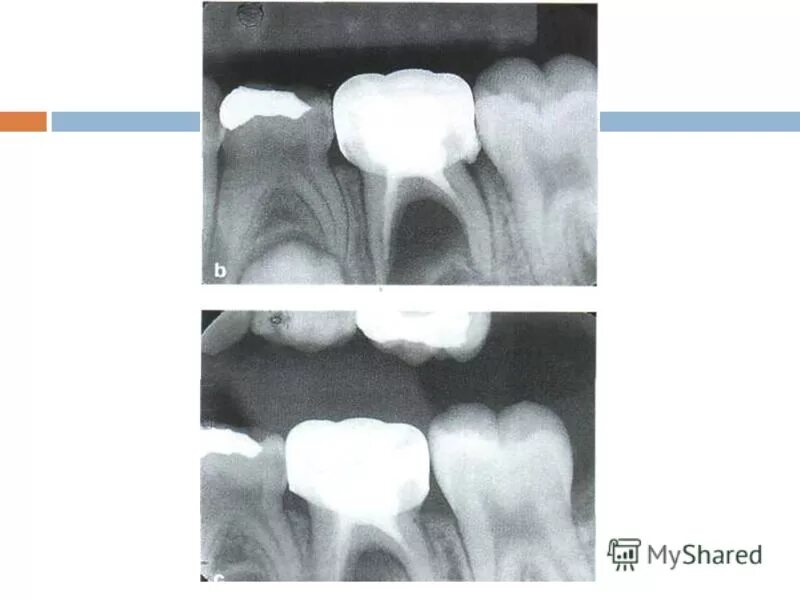

У ребенка нет зачатка постоянного зуба